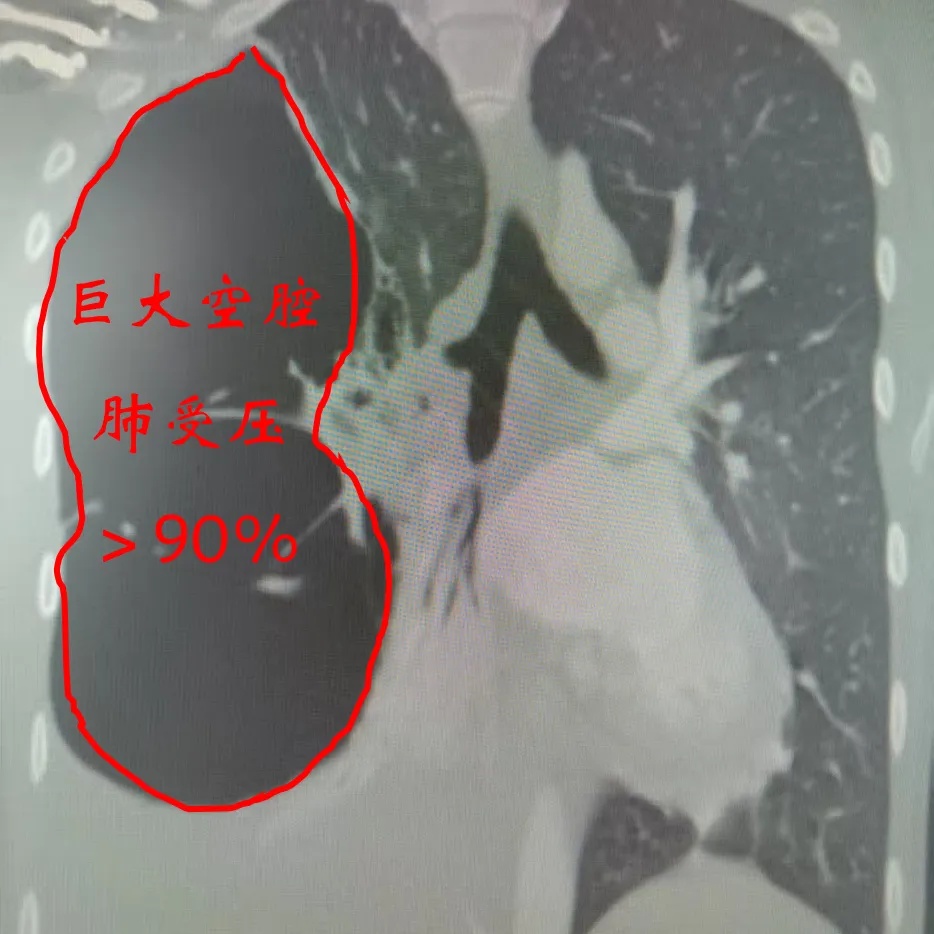

外院诊断结果为右侧脓胸,但经过三个星期的药物治疗,病情未见好转。小郑的父亲抱着最后一丝希望,找到了胸外科郭清奎主任。郭主任详细调阅了小郑的胸部CT等资料,凭借丰富的临床经验,他敏锐地判断这并非单纯的脓胸,极有可能是巨大的支气管囊肿或肺大疱合并感染,继而引发了严重的脓胸。

入院后的检查结果印证了郭主任的判断,小郑的右肺已被压缩了90%以上,情况危急,若再不手术,后果不堪设想。然而,手术的风险同样巨大。由于病程较长,胸腔内解剖结构紊乱,粘连极其严重,原本光滑的胸膜腔可能已经变成了“盘丝洞”,手术操作稍有不慎就可能引发大出血或肺组织损伤。加上患者严重的营养不良和低蛋白血症,术后恢复也是一道难关。